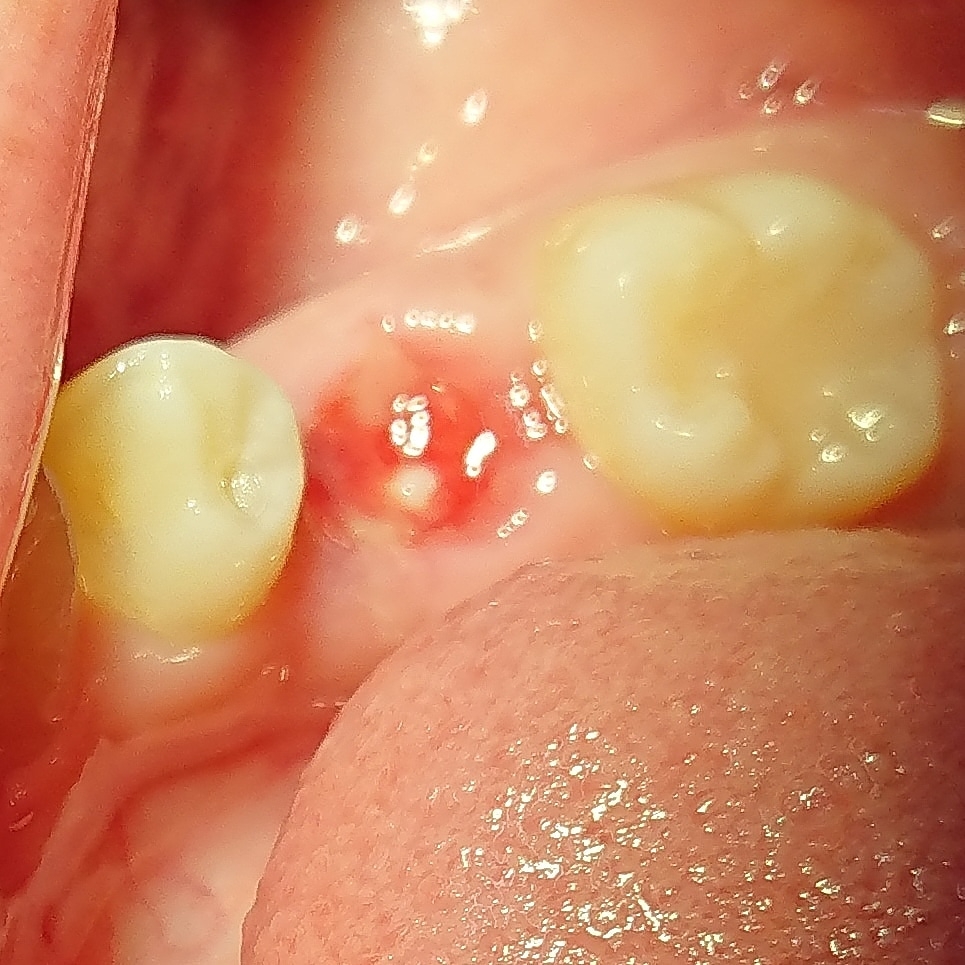

抜歯後の不良肉芽組織の除去はとても大切小嶋デンタルクリニック。

抜歯後の不良肉芽組織の除去はとても大切小嶋デンタルクリニック。